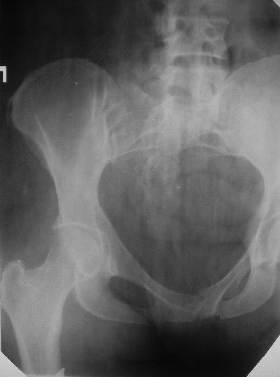

Из анамнеза: в ноябре 2002г. оступилась,упалана трап самолета (на верхней площадке, сразу при выходе из салона) на правый тазобедренный сустав, а затем - вниз на землю на ноги и ягодицы. Потеряла сознание от боли. Доставлена в больницу по месту жительства, лечилась консервативно с диагнозом кокцигодиния.На рентгенограмме от 27.11.02г. вывиха копчика не определяется (снимок идентичен представленной R-грамме от28.11.03г., кроме этого есть нормальная R-грамма копчика в боковой проекции).Через три недели стала ходить, но привести правую ногу в тазобедренном суставе не могла. Сейчас ходит отведя кнаружи правое бедро и голень, как ножку циркуля (фото 1). Неврологических нарушений нет. По просьбе врачаможет на 30-40 секунд поставить ноги вместе (фото 2). При этом испытывает сильную тянущую боль и ощущение "вывернутости" в правом тазобедренном суставе. Эти ощущения заставляют вновь отвести бедро. В положении лежа разогнуть бедро полностью не может из-за болей в ягодичной мышце (фото 3). Сгибание также ограничено из-за болей (фото 4). Отведение в положении лежа возможно в том же объеме, что и стоя (фото 5). Заподозрен старый разрыв правого крестцово-подвздошного сочленения.Выполнено R-исследование и КТ(в приложении). По-поводу деформации лонного сочленения выяснен гинекологический анамнез. Роды одни, нормальные в 22 года. Из роддома выписана на 8 сутки, нарушения походки не было, R-графия таза не проводилась. Вопросы на обсуждение: 1. Диагноз либо алгоритм дальнейшего обследования. 2. Лечебная тактика (в первую очередь возможность и целесообразность оперативного лечения).

Уважаемый Юрий Алексеевич, сделаны ли пациентке более дистальные срезы КТ с захватом области тазобедренного сустава? Учитывая давность травмы, могли присоединиться и дистрофические процессы в субхондральной кости головки и впадины. Изменения в капсуле будут хорошо видны на УЗИ, особенно в сравнении со здоровой стороной. Эффективность лечебно-диагностического введения гормональных препаратов, на мой взгляд, сомнительна ввиду давности патологического состояния. При такой стойкой и давней контрактуре без операции вряд ли можно обойтись. Под наркозом амплитуда на разгибание должна увеличиться, усилить эффект можно тено-миотомиями заинтересованных групп мышц, капсулотомией + в послеоперационном периоде хорошее консервативное противовоспатлительное лечение с укладками на разгибание.Что мешает приведению пока не ясно, во встретившихся в нашей работе аналогичных ситуациях причиной был формирующийся медиальный остеофит головки, выталкивающий её из впадины.

Особенно при медиальных остеофитах и протрузио, когда идет удаление остеофитов по кругу, после удаления нароста рефиксацию лабриум. Без выяснения уровня контрактуры, врядь ли поможет Z-образное удлинение широкой фасции бедра или операция Хельмута.